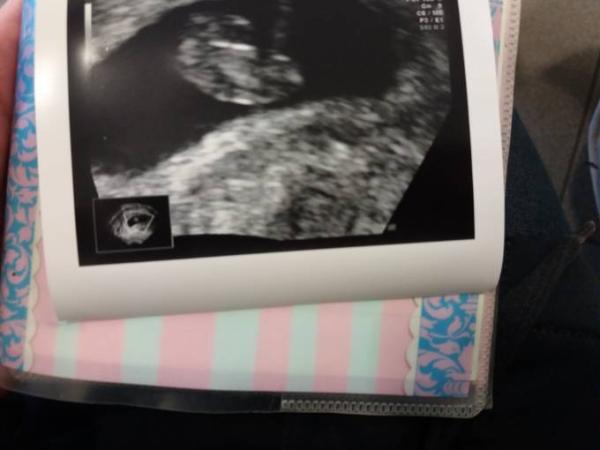

Unserem kleinen Krümelchen geht es sehr gut

das Herz schlägt kräftig und es ist zeitgerecht entwickelt. Entspricht genau meinen Berechnungen, somit ist der ET der 22.07.18.

Siehst du, hab ich doch gesagt! So sieht mein Krümel auch aus, nur schon etwas größer. So schön, das Bild!

Bild sieht prima aus.